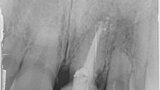

Fig. 8: The resorption of tooth #21, external view. This confirmed the accuracy of the diagnosis from

the imaging procedure.